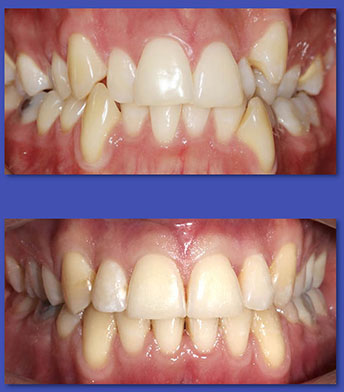

2. PERIODONCIA

La Periodoncia se dedica al tratamiento de las patologías que afectan a las encías y al hueso de soporte de los dientes. Las enfermedades principales son la Gingivitis y la Periodontitis, ambas se manifiestan principalmente por la inflamación y sangramiento de las encías. El tratamiento puede variar desde realizar una correcta técnica de cepillado y el uso de cinta dental, pasando por el destartraje (eliminación de sarro), o el pulido radicular en el caso de las periodontitis.

ANTES

Periodoncia

DESPUÉS